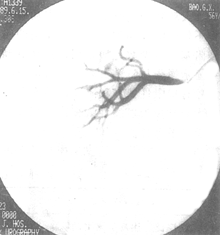

DSA的分辨率足够观察肾实质内直径小至1mm的血管,可诊断肾动脉病变达91.1%,有参考价值者6.6%,只2.3%影像不能作出诊断。DSA可以区分纤维肌肉发育不良、动脉粥样硬化、肾萎缩、肾动脉细小或肾动脉闭塞等症。在显影不够满意的病例,可因肾动脉开口处极度狭窄致使显影剂密度不足而影响肾内血管小分支的浓度,也可因动脉的重叠或心排血量不足所致。DSA可测出肾内血液分布的数值、灌注情况、积蓄功能以及廓清功能等,从而可准确地评估两肾的生理功能(图5、6)。

图5 腹主-肾动脉造影—DSA

图6 肾动脉造影—DSA